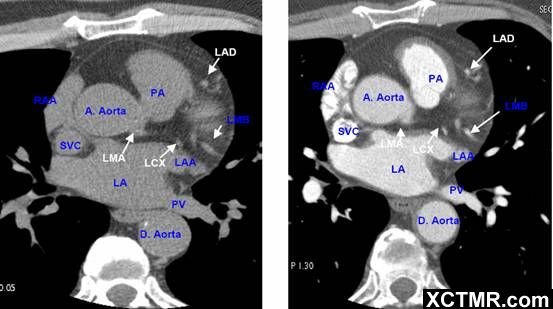

常用英文名称及缩写 LA - Left Atrium 左心房 RA - Right Atrium 右心房 LV - Left Ventricle 左心室 RV - Right Ventricle 右心室 Mitral Valve 二尖瓣 A. Aorta-Ascending Aorta 升主动脉 D. Aorta-Descending Aorta 降主动脉 SVC – Superior Vena Cava 上腔静脉 IVC – Inferior Vena Cava 下腔静脉 PA - Pulmonary Artery 肺动脉 PV - Pulmonary Vein 肺静脉 LMA - Left Main Artery 冠状动脉左主干 LAD - Left Anterior Descending Artery 左前降支 LCX - Left Circumflex Artery 左回旋支 LMB - Left Obtuse Marginal Branch 左边缘支(钝缘支) RCA - Right Coronary Artery 右冠状动脉 PDA - Posterior Descending Artery 后降支 Conus Branch 右动脉圆锥支 LAA – Left Atrial Appendage 左心耳 RAA – Right Atrial Appendage 右心耳 CS - Coronary Sinus 冠状窦 MCV – Middle Cardiac Vein 心中静脉 GCV –Great Cardiac Vein 心大静脉 PIVV – Posterior Intraventricular Vein 后室间静脉(心中静脉) PLVV – Posterior Left Ventricular Vein 左室后静脉 PLV – Posterior Lateral Vein 左室后侧静脉(边缘静脉) | |